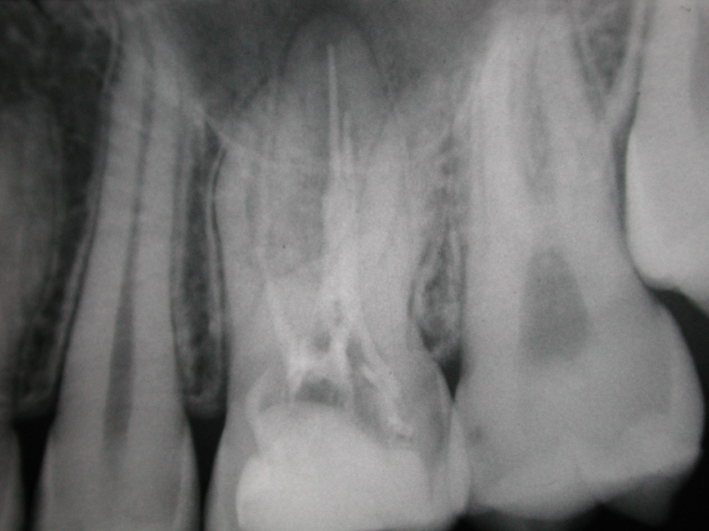

«L’imaging radiografico è fondamentale: dopo la raccolta dei dati anamnestici e un’accurata visita, il primo step è la radiografia periapicale eseguita con la tecnica dei raggi paralleli (centratori). Non sempre, tuttavia, questo esame consente di distinguere tra riassorbimento interno ed esterno; per questo è utile una seconda radiografia, con diversa inclinazione, che grazie alla sproiezione delle immagini può aiutare a chiarire il tipo di riassorbimento. Oggi però sappiamo che l’immagine bidimensionale presenta molti limiti; per questa ragione, le principali linee guida internazionali (AAE-American Association of Endodontists ed ESE-European Society of Endodontology) raccomandano un esame di secondo livello come la CBCT (FOV piccolo, alta risoluzione). Questo consente una diagnosi precisa, informazioni sulla reale estensione del processo distruttivo e, di conseguenza, un piano di trattamento più accurato».

Dal punto di vista biologico, i riassorbimenti derivano dall’attivazione di cellule clastiche capaci di degradare dentina e cemento, stimolate da fattori infiammatori o traumatici. «Le cause più comuni sono traumi, movimenti ortodontici, scaling e carie, ma talvolta il processo decorre del tutto senza sintomi. Clinicamente, i riassorbimenti radicolari possono restare occulti a lungo e venire diagnosticati solo con indagini radiografiche o, più recentemente, con CBCT, che ha migliorato la comprensione di localizzazione ed estensione del difetto, distinguendo chiaramente tra quadri interni ed esterni, distinzione fondamentale per strategie e prognosi».

Diagnosi corretta e comunicazione chiara sono gli elementi fondamentali per una valutazione prognostica precisa e una scelta terapeutica calibrata sul caso, ricorda Marcoli. «La diagnosi radiografica tradizionale o la CBCT, se necessario, permettono di stabilire se il riassorbimento sia di origine interna o esterna, se vi sia comunicazione con il parodonto e quanto sia esteso il difetto. Una volta fatta la diagnosi, la scelta terapeutica dipende da vari fattori: localizzazione ed estensione del riassorbimento, vitalità della polpa, grado di compromissione dei tessuti duri e condizioni generali del paziente». Questi elementi consentono di distinguere tra forme potenzialmente trattabili e forme irreversibili. «Nei riassorbimenti esterni infiammatori talvolta la rimozione dell’endodonto può determinare l’arresto del processo; quelli sostitutivi, invece, legati a traumi o reimpianti, hanno prognosi sfavorevole: il processo di sostituzione radicolare con osso è progressivo e irreversibile, e la terapia mira solo a prolungare la sopravvivenza del dente. Nei riassorbimenti interni, al contrario, il trattamento endodontico ortogrado è la scelta di elezione. L’obiettivo è interrompere il processo infiammatorio eliminando il tessuto pulpare alterato e sigillando stabilmente la cavità di riassorbimento. L’introduzione di materiali bioceramici e tecniche di otturazione dedicate ha ampliato le possibilità di successo. L’approccio ottimale resta quello personalizzato: riconoscere precocemente il tipo di riassorbimento e adottare una strategia mirata, sfruttando le risorse diagnostiche e i materiali oggi disponibili».

Per quantificare la perdita radicolare, gli autori hanno analizzato radiografie digitali pre e post-trattamento, misurando la lunghezza degli incisivi superiori e inferiori.